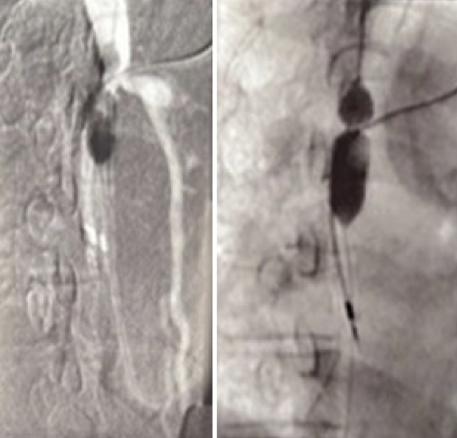

Une tomodensitométrie thoraco-abdomino-pelvienne avec et sans injection est réalisée. Elle retrouve une veine cave sténosée d’aspect très serré (fig. 2), expliquant les varices thoraco-abdominales. Ces dernières servent de réseau de suppléance au système cave supérieur et drainent ainsi la partie supérieure du corps. Le patient est hospitalisé en chirurgie thoracique et cardiovasculaire afin de bénéficier d’une dilatation cave supérieure par voie endoluminale (fig. 3), sans pose de stent.